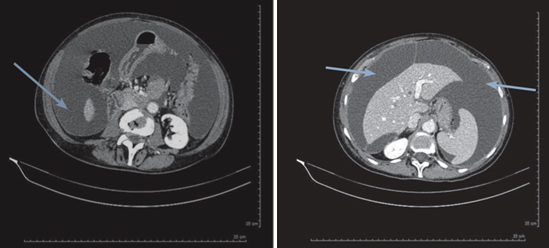

Suppression par le catumaxomab d’une ascite invalidante chez une patiente souffrant d’une carcinose péritonéale liée à un cancer de l’ovaire

L’ascite carcinomateuse est une complication fréquente des cancers épithéliaux de l’ovaire, dont le traitement peut s’avérer difficile en raison d’une résistance à la chimiothérapie, alors que celle-ci est efficace sur les autres cibles.

Cette ascite s’accompagne souvent de symptômes invalidants : douleurs, distension abdominale, signes de compression vésicale ou intestinale, baisse de l’état général ou encore dyspnée (1).